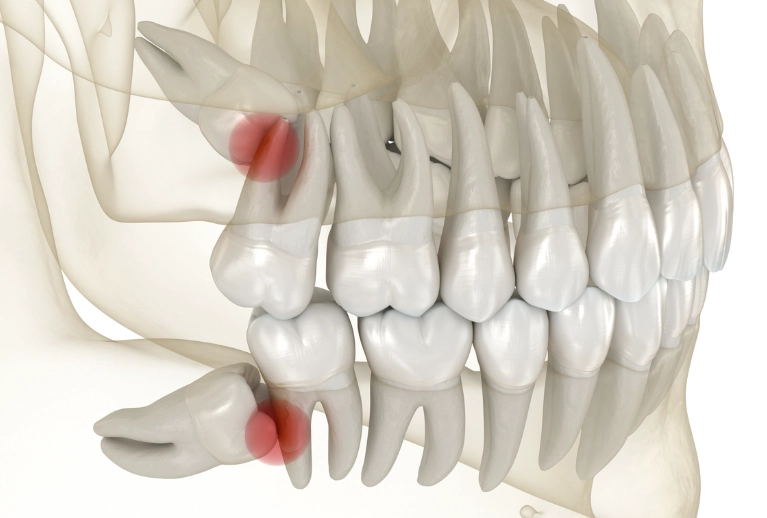

Pericoronitis: The Infection You Can Feel

This is a big one. When a wisdom tooth partially erupts, a flap of gum tissue often remains over it. This flap is a perfect trap for food particles and bacteria. The resulting infection—pericoronitis—causes intense, localized pain, swelling, a bad taste, and sometimes difficulty opening your mouth. It's a clear signal that the area is no longer manageable with brushing alone.

Crowding and Decay

Even if a wisdom tooth manages to come in fully, it's often so far back and angled so awkwardly that it's impossible to clean properly. Plaque builds up rapidly, leading to cavities in the wisdom tooth itself and the precious molar in front of it. The pain from this decay can be sharp and sensitive to temperature or sweets.

The Problem of Impaction

An impacted wisdom tooth is one that fails to fully emerge through the gums. It gets stuck. This is the core issue for most severe pain cases. The type of impaction dictates the kind of trouble you'll have.